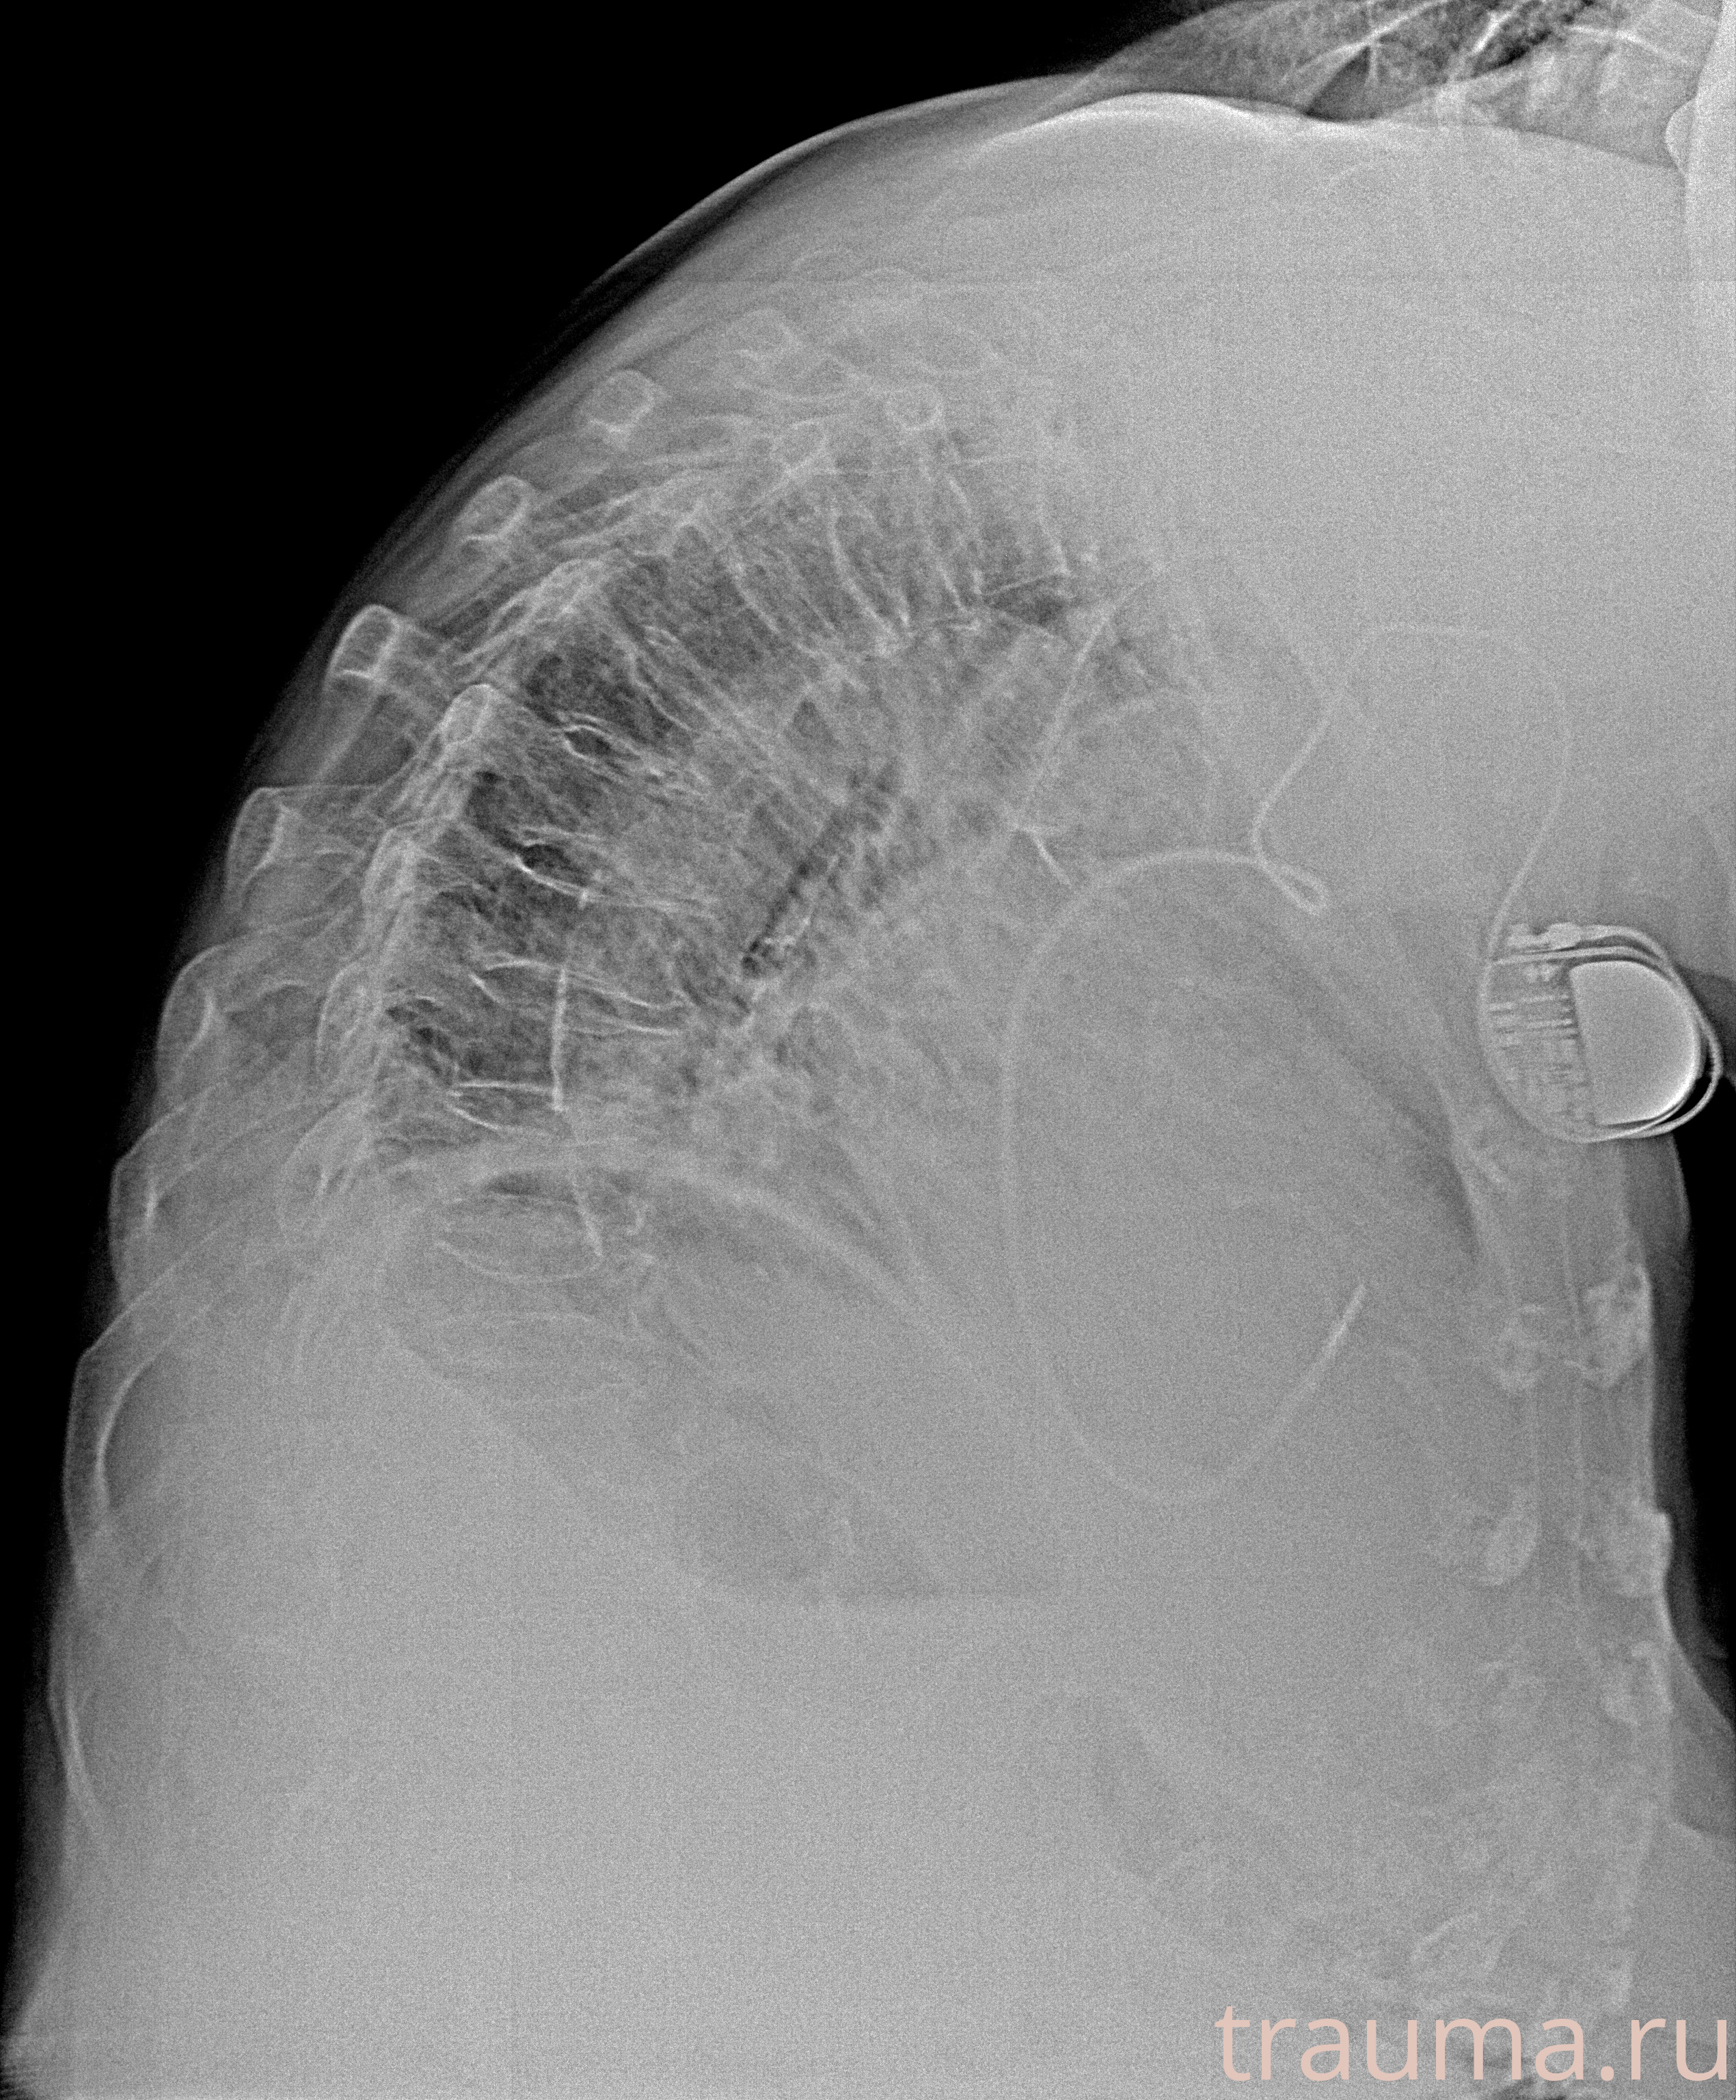

Рентгенограммы

Рентген на дому: по вашему адресу приезжает врач-рентгенолог, травматолог-ортопед с мобильным рентгеновским аппаратом, проводит диагностику травмы или заболевания, делает необходимые рентгенограммы, дает рекомендации по дальнейшему лечению. Получить качественные снимки в домашних условиях возможно благодаря уникальной методике, разработанной МосРентген Центром для института  Склифосовского